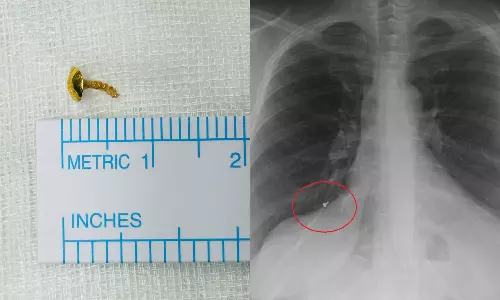

സ്വകാര്യ ആശുപത്രിയിൽ നടത്തിയ സ്കാനിങ്ങിലാണ് ശ്വാസകോശത്തിൽ എന്തോ തറഞ്ഞിരിക്കുന്നതായി കണ്ടെത്തിയത്.